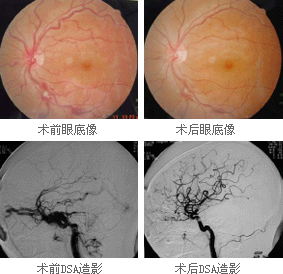

1、腦血管造影間接型頸動脈海綿竇瘺腦血管造影檢查的目的是確定瘺口的位置,供血動脈,靜脈引流形式,有無頸外動脈系統與頸內動脈系統和椎動脈系統的“危險吻合”等。腦血管造影檢查的內容包括患側頸內動脈的選擇造影,患側的椎動脈,頜內動脈,咽升動脈造影和對側頸內動脈和頸外動脈的選擇造影。微導管超選擇造影可進一步了解各供血動脈的供血情況。正常情況下,海綿竇接受眼上、下靜脈和蝶頂竇的引流,再經岩上、下竇引流到橫-乙狀竇交界處和頸靜脈球。兩側的海綿竇經海綿間竇相交通。在CCF存在的情況下,海綿竇內壓力增高,血流方向發生改變:經眼上靜脈逆流入角靜脈和面靜脈,經海綿間竇注入對側海綿竇,以及逆流入蝶頂竇等。此類頸動脈海綿竇瘺的供血情況通常非常複雜。在經動脈途徑栓塞治療前,必須仔細研究腦血管造影,特別注意有無“危險吻合”的存在。頸總動脈分叉處的情況也是腦血管造影要觀察的重要內容。如果該處有動脈粥樣硬化斑塊,則禁止採用壓迫頸總動脈的方法治療間接型頸動脈海綿竇瘺。

2、CT和MRI掃描可顯示擴張的眼上靜脈和其他眼部繼發性改變,還能發現腦水腫和顱內出血;MRI上可發現瘺口緊鄰硬腦膜處有“流空”現象。

間接型頸動脈海綿竇瘺(2)經靜脈栓塞:由於間接型頸動脈海綿竇瘺往往有多支動脈供血,經動脈栓塞困難較大,未栓塞的供血支會逐漸擴張,瘺口重新開放,因此也可採用經靜脈栓塞術。常用方法是手術暴露眼上靜脈,將導管插入靜脈並注入微彈簧圈及硬化劑,瘺口可完全栓塞。此外,還可經頸內靜脈-乙狀竇-岩上竇或岩下竇到海綿竇,用栓塞劑栓塞海綿竇閉塞瘺口。栓塞劑有彈簧圈、液體粘合劑、真絲線段、可脫球囊等。可脫球囊已較少套用,因為輸送球囊的導管比較粗大,會將靜脈擴張,造成損傷;液體膠有流出瘺口、阻塞眼上靜脈和其他正常靜脈的危險;鉑制彈簧圈可通過微導管輸送,可操作性強,是目前套用廣泛的栓塞物。